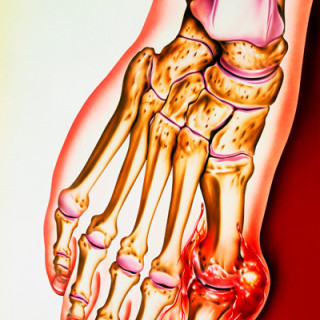

Anne Voss, Claus Manniche, Dženan Mašić et al. Reumatologi 4. utg. 543 s, tab, ill. København: FADL's Forlag, 2018. Pris DKK 800 ISBN 978-87-7749-969-2 Denne danske læreboken i revmatologi består av 27 kapitler om revmatologiske sykdommer. Rundt 50 forfattere bidrar og kommer utelukkende fra det danske revmatologiske miljøet. Målgruppen er angitt til å være leger, men også kiropraktorer, fysioterapeuter og andre med interesse for revmatologi. Boken brukes i spesialistutdannelsen for faget revmatologi i Danmark, og som oppslagsverk for ortopeder og allmennleger. Den virker også adekvat for...